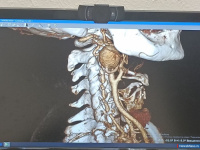

В Челябинской областной клинической больнице (ЧОКБ) врачи сосудистой хирургии провели сложную операцию по удалению аневризмы внутренней сонной артерии у 59-летней пациентки из Миасса. Аневризма - растяжение стенки важнейшего сосуда на шее - увеличилась в десять раз, достигнув опасных размеров. По оценкам специалистов, риск разрыва аномалии в течение года составлял от 30 до 40%. Лопнуть аневризма могла в любой момент - из-за скачка давления, падения или удара. Последствия такого события были бы... [далее]